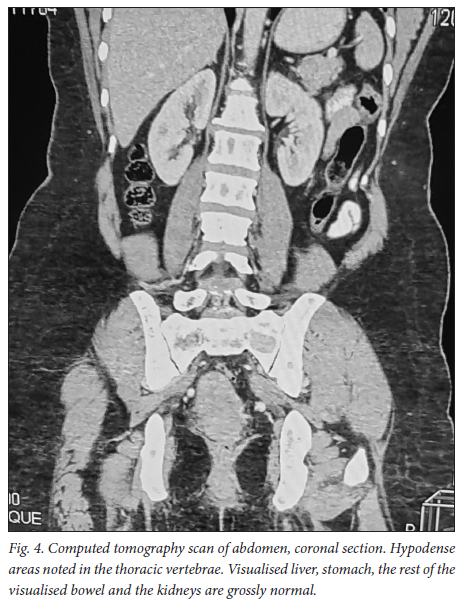

A 39-year-old obese woman had had a lump in the right breast for 18 months. She had gone to her local hospital when she noticed the lesion. A core biopsy was done and she was referred to the breast oncology clinic at Mankweng Hospital in Polokwane, Limpopo Province, South Africa, for further assessment and management. She had previously been healthy, with no known comorbidities and no family history of malignancy. On enquiry about her gynaecological history, she stated that her menarche had been at age 12, and she was still having normal periods and on contraception. She had a 15-year-old child, born when she was 24. After the birth of this child she had two more pregnancies, both resulting in unexplained stillbirths at term. She had no history of pregnancy-induced hypertension or any medical conditions diagnosed during pregnancy. After her discovery of the breast lump she was diagnosed with young-onset hypertension. There were no associated weight changes, and she was HIV negative. On examination she had a scar on the right upper quadrant, no palpable axillary lymph nodes, an elevated blood pressure (150/93 mmHg, pulse rate 88 bpm) and a high body mass index (37.7 kg/m2). The rest of the vital signs and the findings on systemic examination were unremarkable. On examination of the breast, the tumour was clinically staged as T3N0M0, making it stage IIB. Histological evaluation showed nests of cells infiltrating extensively throughout the tissue. The cells were hormone receptor (oestrogen and progesterone) positive, the HER2 score was 3+ and the Ki-67 proliferation index was 50 - 60%. Synaptophysin (SYP) and chromogranin (CGA) cytoplasmic staining was positive within the tumour cells, features in keeping with grade 3 invasive carcinoma showing neuroendocrine differentiation. A mammogram (Fig. 1) revealed poorly marginated density with a speculated mass noted on the upper inner quadrant at 1 o'clock on the middle portion of the right breast. The mass expended anteriorly to the retro-areolar space causing minimal traction of the peri-areolar skin and nipple. There were associated architectural distortions and trabecular thickening. The retromammary space was grossly normal bilaterally. There was no thickening of overlying skin, and no dilated ducts bilaterally. Regional benign calcifications were noted in the left breast. No axillary lymph nodes were visualised bilaterally. For further evaluation, a computed tomography (CT) scan (Figs 2, 3 and 4) was done and revealed multiple enlarged lymph nodes in the right axillary region. The right breast was ill defined with trabecular thickening and nipple retraction. The breast mass did not extend into the retromammary space, and the pectoralis muscle was grossly normal. Hypodense areas were noted in the thoracic and lumbar vertebrae, with involvement of the posterior elements. The right scapular blade and spine also had multiple hypodense areas. The lung parenchyma, the visualised liver, the stomach and the rest of the visualised bowel and the kidneys were grossly normal. With this evidence, the patient was diagnosed as having primary NEBC, with features suggestive of metastasis to the bones. A bone scan revealed widespread metastases in the skull and throughout the spine, pelvic bone, proximal femur and sternum. In view of this finding, the patient was re-assessed as having clinical stage IV disease. The management approach changed to focus on palliative care. There was no surgical intervention, and the patient was referred to the medical oncology clinic for further management, to come back if the need for surgical palliation arose.

Primary NEBCs are rare and the diagnosis therefore depends on excluding metastasis from other sites, because the two entities require different management approaches.[9] Diagnostic tools include the use of tumour markers such as CGA and SYP immune reactivity, which is significantly associated with a neuroendocrine neoplasm.[1,10] Importantly, elevated CGA levels are also associated with hypertension, obesity and heart failure,[11] among other conditions. On breast imaging with mammography and/or ultrasound, secondary NEBCs are oval in shape, with circumscribed or microlobulated margins.[12] Triple assessment is mandatory; however, histopathological assessment and immunohistochemistry staining are the mainstay of diagnosis. [1,13,14] Clinically, the presentation of NEBCs cannot be distinguished from other types of breast cancer. It has also been postulated that, unlike other breast cancers, NEBCs can present with clinical features related to hormonal secretion because of ectopic production of adrenocorticotrophic hormone, norepinephrine or calcitonin.[15] Our patient was obese and hypertensive, with SYP- and CGA-positive cytoplasmic staining within the tumour cells. More knowledge and research on the possible association between the tumour markers and clinical syndromes could play a vital role in patient management, so further evidence on this association is of crucial importance. So far, there are no available research data specifying radiological pathognomic features in the diagnosis of NEBCs. As in our patient, mammographic and CT scan findings are similar to those in other histologically different types of breast cancer, and imaging therefore cannot be used alone. It is vital to distinguish between primary NEBCs and metastatic neuroendocrine tumours from another site, because treatment of the two is different.[15] The CT scan findings in our case suggested that the patient had advanced breast cancer with metastasis to the thoracic vertebrae, right scapular blade and spine. With no specific management strategies for advanced neuroendocrine breast malignancies, the management principles are currently the same as for other types of breast cancers. A multimodality therapeutic strategy includes chemotherapy, endocrine therapy, peptide receptor radionuclide therapy, radiation therapy or surgery, or combinations of the above. It is hoped that better knowledge of the biology of these tumours will provide new therapeutic targets for personalised treatment in the near future.